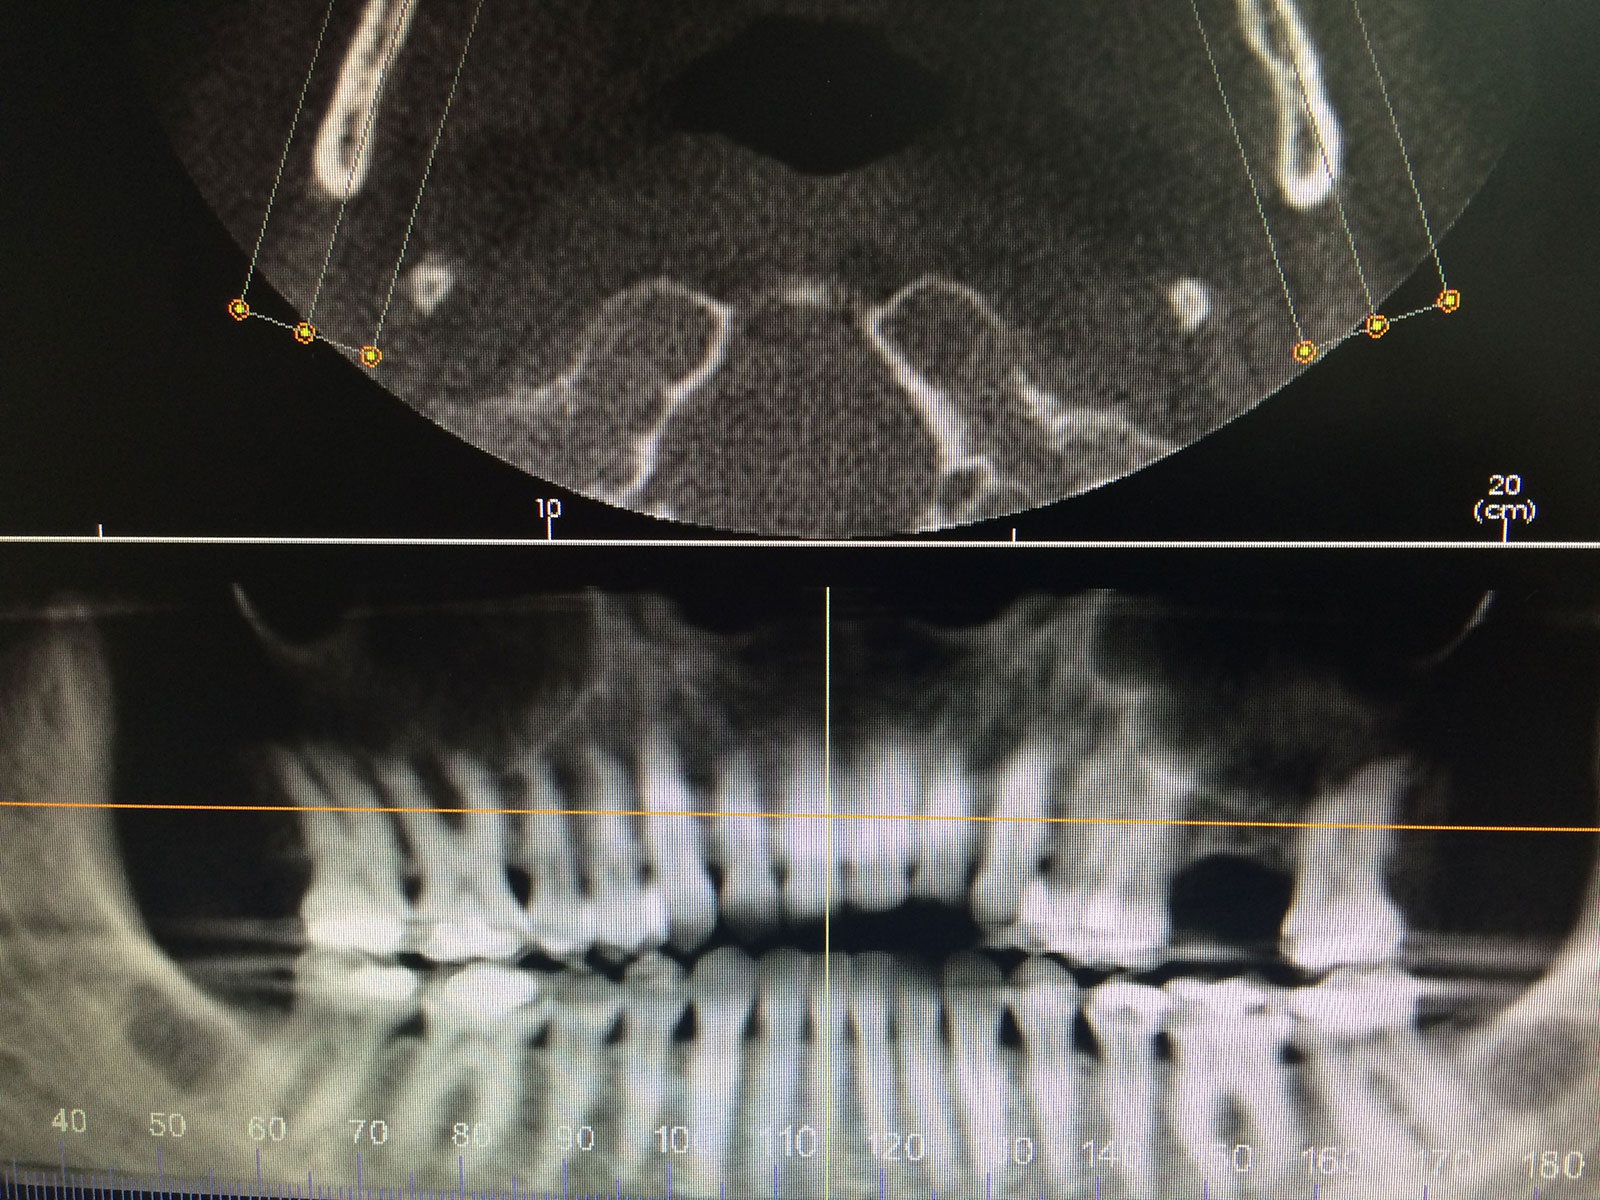

Sinus Grafting Procedures

A sinus grafting procedure, also known as a sinus augmentation, is for patients who have insufficient natural bone in the areas where dental implants are needed. They are long lasting, strong and sturdy, and fit and function like natural teeth. The procedure involves adding bone, either your own natural bone from another part of the body, from a donor or made of processed or synthetic bone material, and placing it below the sinus so that the implants can be placed. After the bone has healed and developed, usually around four to 12 months, the dental implants can be placed.

The photos on this website are from real surgeries performed by Dr. Ulloa. Due to the

graphic nature of the images and content, viewer discretion is advised.

Click to enlarge images